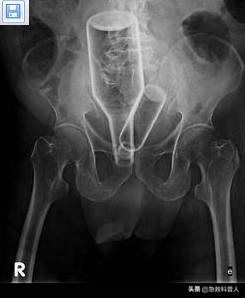

但也并不是完全没有可能,请看图片:

不过,这种情况就不要急救了。也急救不了。赶紧去医院吧!可能要做手术才能解决。此时卡在肛门的异物也不致命。